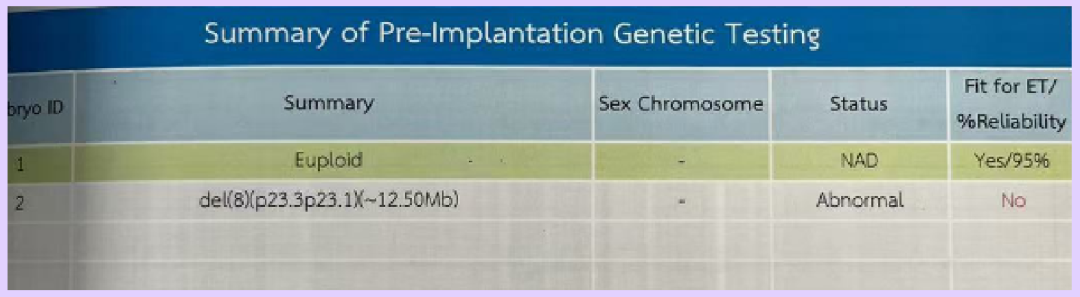

- Chromosomal Screening: 1 normal embryo

▲ Ms. A’s blastocyst culture report

▲ Ms. A’s embryo screening report